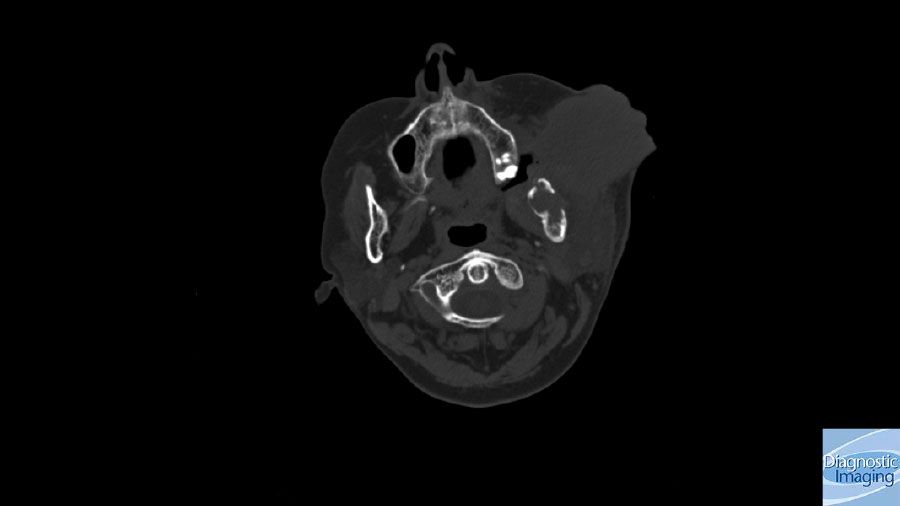

Case History: 49-year-old patient with large buccal mass, history of leakage through mass.

Case History: 49-year-old patient presents with large buccal mass on left side, history of leakage of oral contents through mass.